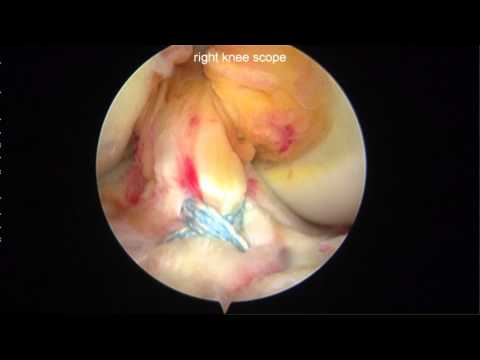

Tibial Eminence Fracture

Tibial Spine Avulsion Fractures Arthroscopic Reduction and Internal Fixation - Dr. Jazrawi

Dr. Jazrawi and Dr. Strauss discuss their technique for tibial spine avulsion fracture fixation